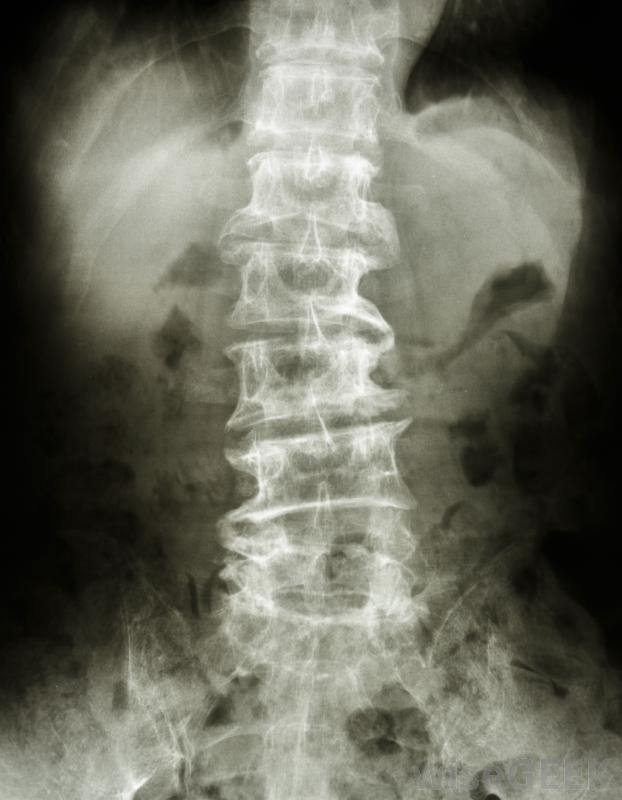

椎間盤切除術和椎板切除術的區別在于手術所涉及的脊柱部位。兩種手術都是為了緩解因脊髓神經卡滯而引起的疼痛,但椎間盤切除術是在椎間盤上進行的手術,椎板切除術是對脊椎椎弓形部分的手術。椎間盤切除術和椎板切除術的區別很重要,因為錯誤的手術可能無法緩解患者的疼痛。

脊椎,或者疊在一起或者融合在一起。脊椎融合的部分組成了骶骨和尾骨,剩下的24個椎骨則堆積起來。在椎骨內,脊髓從大腦向下延伸到下腰部。此時,脊髓分裂成神經集合,其中一些它們通過脊椎的縫隙進入人體。每個椎骨之間有椎間盤,當脊柱彎曲或扭曲時,這些椎間盤起到緩沖作用。這些椎間盤還保持椎骨之間的間隙開放,以便神經可以安全地通過。

隨著時間的推移,位于椎骨之間的椎間盤可能會滑出原位或退化。椎骨中也會形成骨刺,壓迫敏感神經。如果椎間盤滑出原位,柔軟的中央部分會壓迫神經,導致腿部和背部疼痛,如果椎間盤退化,神經通過的開口會變小,導致神經受壓這兩個事件之間的差異是椎間盤切除術和椎板切除術之間區別的根源。

椎板切除術是一種椎板切除術。椎板是椎骨的弓形部分。在椎板切除術中,外科醫生會切除導致神經受壓的部分骨頭。椎板切除術也常見于切除椎板切除術引起神經疼痛的椎間盤或腫瘤的一部分。

滑倒,中央部分壓迫神經。椎間盤的軟中心被切除了,但堅硬的外部部分被保留了。椎間盤切除術和椎板切除術是兩種不同的手術,它們原本是相同的。最初,椎板切除術用于兩種問題。今天,椎間盤切除術切除了部分椎間盤,椎板切除術切除了部分椎板。